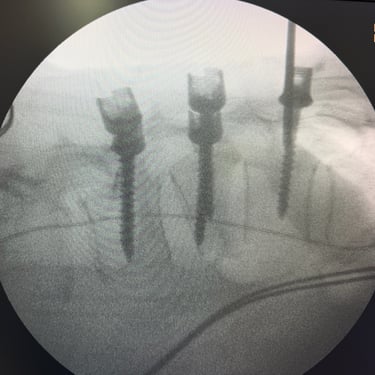

Fractura vertebral lumbar – Artrodesis con tornillos transpediculares (FTP).

La fractura vertebral lumbar es una lesión que puede comprometer la estabilidad de la columna y generar dolor, deformidad o déficit neurológico. En casos seleccionados, el tratamiento quirúrgico mediante artrodesis con tornillos transpediculares (FTP) permite una fijación firme de las vértebras afectadas, restaurando la alineación y brindando estabilidad inmediata. Esta técnica reduce el dolor, previene el desplazamiento vertebral y protege las estructuras neurológicas. La intervención oportuna, junto a una adecuada rehabilitación, favorece una recuperación funcional segura y mejora significativamente la calidad de vida del paciente.